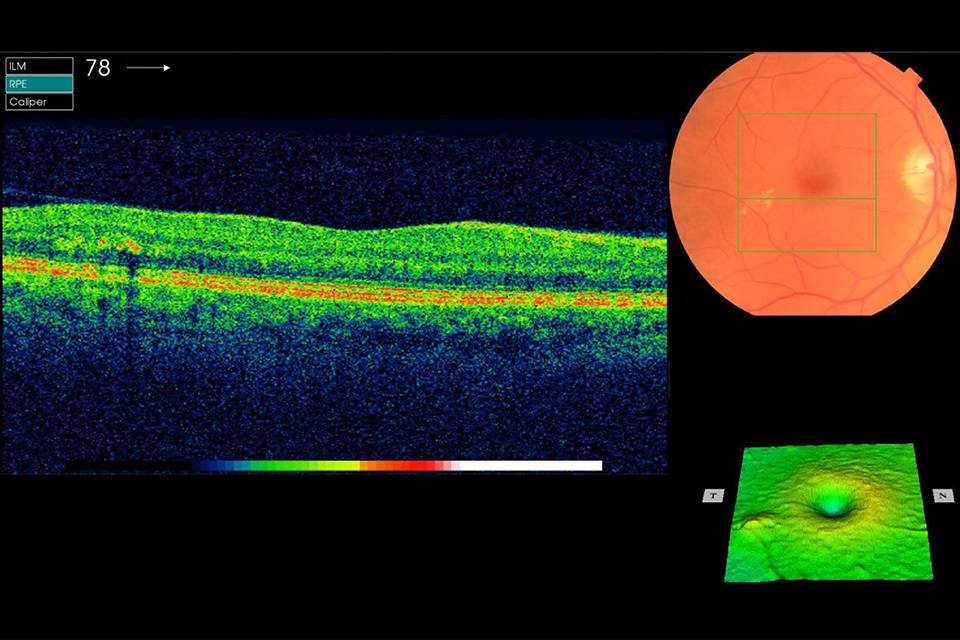

OCT images of retina Example 9 R1M1 and OCT positive

Example 9 shows significant central thickening. It has:

- photographic surrogate markers for M1

- intraretinal cysts

- significant change in foveal contour

- significant diffuse retinal thickening more than 400 µm

Outcome: refer to HES soon and within 4 weeks for Anti-VEGF if central subfield thickness more than 400 µm. The referral outcome grader must refer routinely within the software and make a note on the HES referral recommending a 4 week appointment.